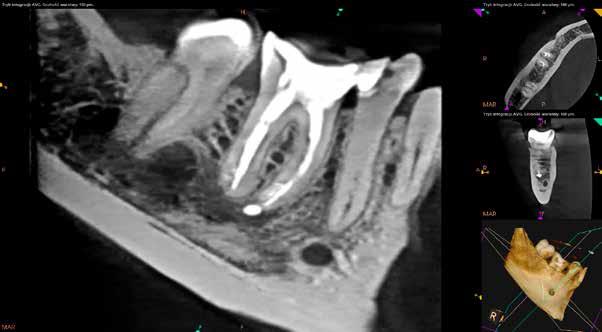

Mind a periapicalis röntgenfelvétel, mind a CBCT-felvétel igazolta, hogy a fragmentum mélyen a gyökércsatorna görbülete mögött, az apikális harmadban helyezkedik el a mesiobuccalis csatornában, valahol a mesiolingualis csatornával történő egyesülés után. Ezenfelül mind a mesialis, mind a distalis gyökércsúcs körül periapicalis gyulladás jelei voltak megfigyelhetőek (1–3. ábra). A betört eszköz nagyjából 5 mm-es hosszúsággal rendelkezett. A mesiolingualis csatornán keresztül a betört fragmentum mellett történő további gyökércsatorna-megmunkálást kockázatosnak ítéltük, mivel nagy esélyt láttunk rá, hogy így a másik eszköz is eltörik, amely pedig a gyökértömés elkészítését nehezítette volna. Azonban a SWEEPS technológiának és a biokerámia sealereknek köszönhetően más megoldási lehetőségek is nyitva álltak előttünk.

2. ábra: Kiindulási CBCT-felvétel. A betört eszköz mélyen a gyökércsatorna görbülete mögött található.

3. ábra: A betört eszköz vége jóval a mesiobuccalis és mesiolinguális csatorna egyesülésének pontja alatt helyezkedik el.

A páciens a jobb alsó első nagyőrlőfogából kiinduló közepes erősségű fájdalom miatt kereste fel a rendelőnket. Periapikális röntgen és CBCT-felvétel is készült. Mindkét felvétel a mesiobukkális gyökércsúcs körül található radiolucens elváltozás jelenlétét igazolta. Ezenfelül a mesialis gyökérben két betört eszközdarab is észlelhető volt. Az egyik a középső gyökéri harmadban a gyökérgörbület előtt volt megtalálható, a másik pedig kicsivel a gyökérgörbület után (12–13. ábra).

A CBCT-felvételen a fog mindkét gyökércsúcsa körül radiolucens elváltozás volt észlelhető (26. ábra). Ezenfelül a periapikális felvételen a mesiobuccalis gyökérben egy betört eszközt is felfedeztünk (27. ábra).